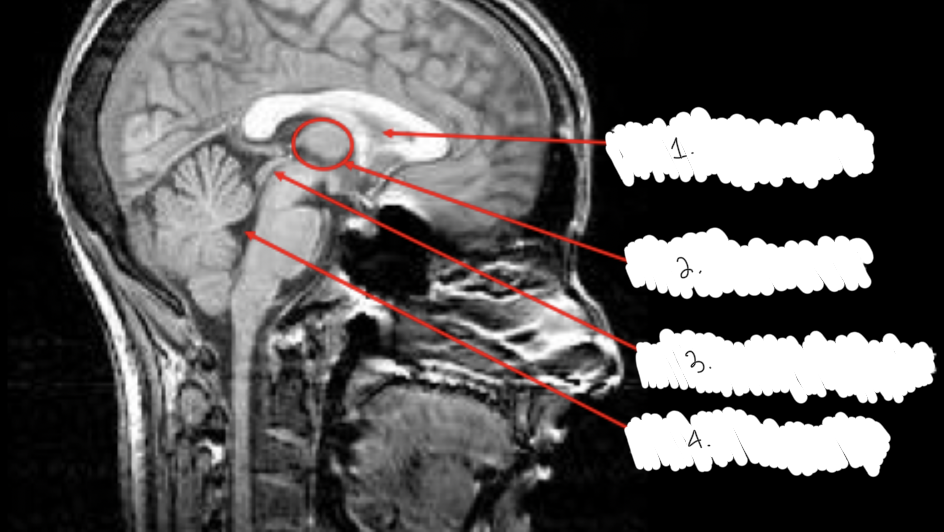

label this diagram

1: lateral ventricle

2: third ventricle

3: cerebral aqueduct

4: fourth ventricle